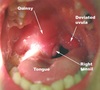

Bacterial: higher fever that gets worse a few days into illness rather than better, longer course over 10-14 days, possible pus on tonsils

When should you prescribe antibiotics and if prescribing antibiotics for a sore throat (e.g pharnygitis or tonsillitis), what are the antibiotics of choice?